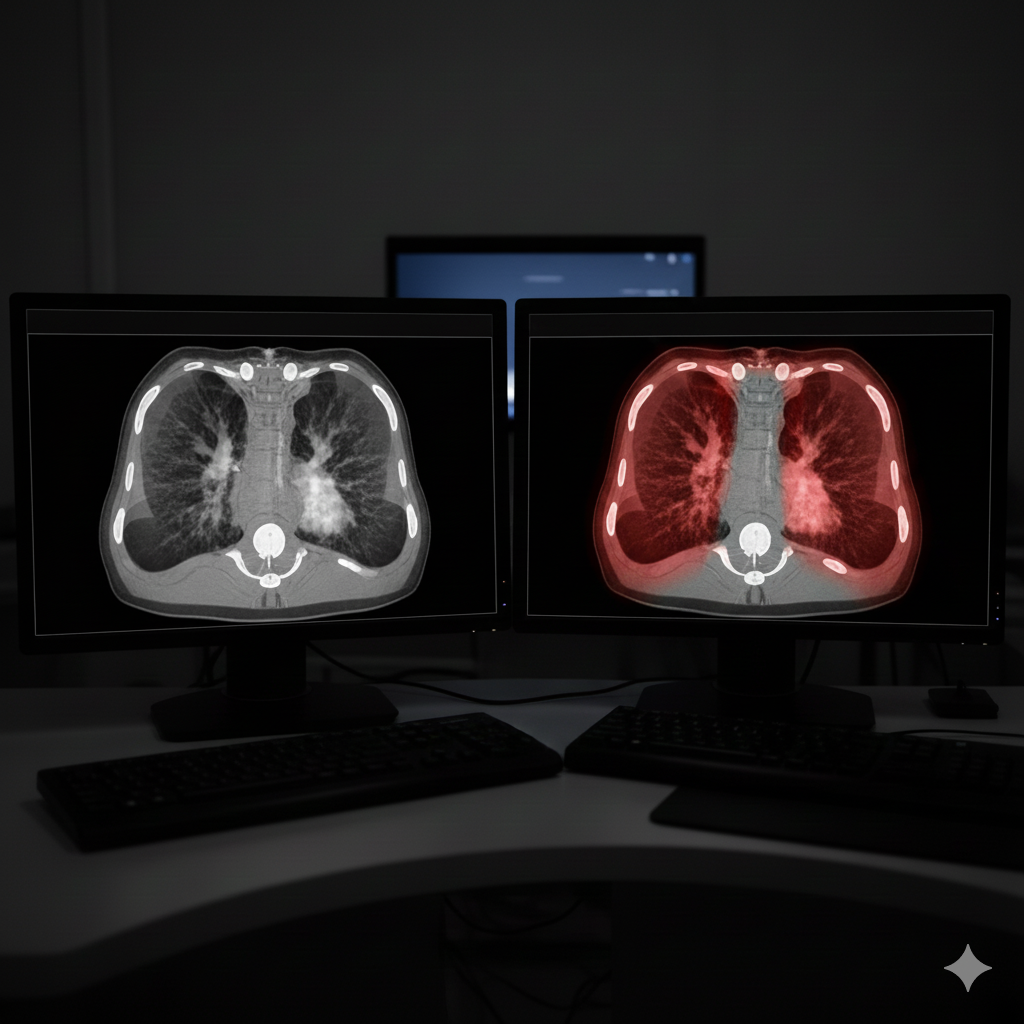

Por exemplo, na análise de TC de pulmões, o sistema pode quantificar a porcentagem de tecido pulmonar afetado por pneumonia, o que é criticamente importante para determinar a gravidade do estado do paciente. No exame de mamografias, a IA ajuda a detectar microcalcificações e neoplasias em estágios muito iniciais, atuando como um sistema de dupla verificação que minimiza o risco de deixar passar uma patologia.

Comparação da visualização de TC pulmonar: original e área de patologia destacada pela IA

A IA destaca e quantifica áreas de lesão em imagens médicas, fornecendo dados objetivos ao médico